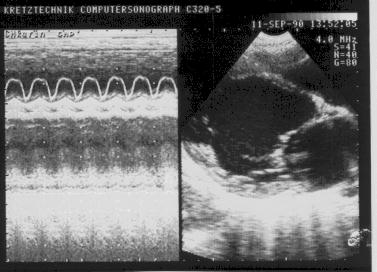

Дилатационная кардиомиопатия (1).

Рис.144

Дилатационная

кардиомиопатия:

увеличение

митрально-септальной

дистанции.

Дилатационная кардиомиопатия (2).

Рис.145

кардиомиопатия,

относительная

недостаточность

митрального клапана,

пассивное движение

межжелудочковой

перегородки.

8. Увеличение митрально-септальной дистанции (точка Е митрального клапана-левая сторона МЖП) (рис.3).

2. Относительная недостаточность митрального клапана (рис.145).